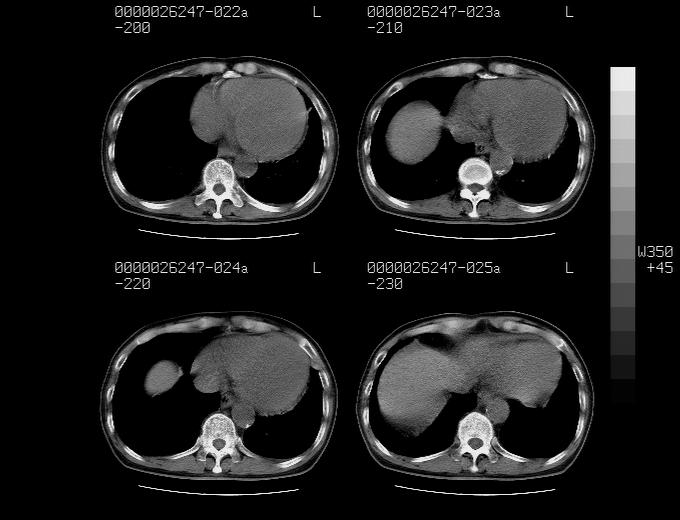

感谢各位老师的意见,左上肺病灶,我本人趋向结核,原因:左上肺见两个类圆形结节,仔细回顾4月份ct似乎原片在该处有条片状密度增高影,强化不明显。

现上传增强片,请各位老师仔细帮我看一下。

右上肺可见条索状影,并可见钙化,左上肺结节可以考虑为结核球,但气管前腔静脉后有肿大淋巴结,本人觉得左上肺结节不能排除转移瘤的可能,右上肺为陈旧性结核灶。

左肺上叶周围性肺癌并纵隔多组lnm.不可能是tb.

左肺上叶尖段瘢痕癌并纵隔淋巴结转移解释更好一些.

双上肺继发型肺结核,纵隔淋巴结结核可能性大,建议定期复查.

1)左肺上叶尖段周围型肺癌并纵隔淋巴结转移。2)冠状动脉及主动脉钙化。